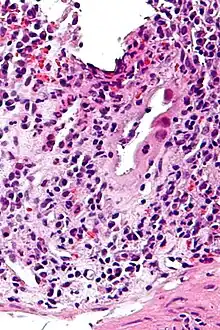

| Micrograph of CMV colitis. H&E stain. | |

CMV colitis may be clinically manifested with diarrhea (usually non-bloody), abdominal pain, weight loss and anorexia. The diagnosis of CMV colitis is based on serology, CMV antigen testing and colonoscopy with biopsy. Clinical suspicion should be aroused in the setting of immunocompromised patient but it is much rarer in immunocompetent patient. Although it is known that CMV colitis is almost always caused by reactivation of latent CMV infection in immunocompromised patients, new infection of CMV or reinfection of different strain of CMV can cause colitis in immunocompetent hosts. Because asymptomatic CMV viremia and viruria is common and about 1/3 of symptomatic CMV infection is caused by reinfection of different strain of CMV, the diagnosis of CMV colitis needs more direct causality. It is practically achieved by colonoscopy or sigmoidoscopy tissue sampling and pathological evidence of CMV infection under microscope, more specifically macroscopic picture will show many ulcers that appear on the mucous membrane and microscopically the biopsy will show intranuclear and cytoplasmic inclusion bodies. Positive CMV IgG doesn't necessarily mean that it is reactivation of latent infection because of the possibility of reinfection of different strain.